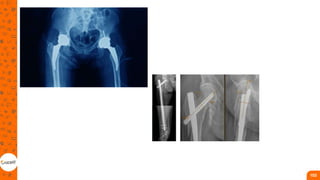

Fraturas de MMII

Fratura proximal do fêmur

• São frequentes na população idosa e,

na maioria das vezes, decorrentes de queda

de altura, sendo consideradas um dos

maiores problemas de saúde pública do

mundo, pela alta mortalidade e

incapacidade funcional;

• podem ser divididas em colo femoral,

transtrocantéricas e subtrocantéricas

Proximal de fêmur

• O tratamento cirúrgico é indicado

por gerar estabilidade e um

retorno funcional mais precoce.

O tratamento não cirúrgico é

normalmente reservado apenas

para pacientes críticos, instáveis

clinicamente para a cirurgia ou

pacientes não deambuladores.

1. hastes cefalomedulares - indicadas para as

fraturas transtrocantéricas e

subtrocantéricas;

2. placa e parafuso - indicados para as

fraturas do colo do fêmur e

transtrocantéricas;

3. parafusos - indicados para as fraturas do

colo femoral de grau I e II de Garden;

4. próteses parciais ou totais do quadril -

indicadas para idosos com fraturas do colo

de fêmur de grau III e IV de Garden.

Fratura de diáfise do fêmur

• A haste intramedular (HIM) é o

tratamento mais comum em

pacientes fisiologicamente

estáveis;

• A fixação externa é indicada

para pacientes com fraturas

expostas, lesões vasculares,

politrauma e estabilização para

transferência;